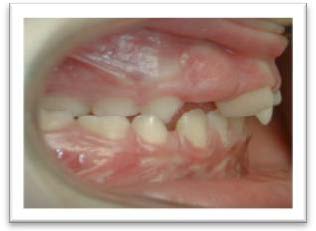

Canine(s) incluse(s) avec risque de résorption de l'incisive latérale

Béance antérieure